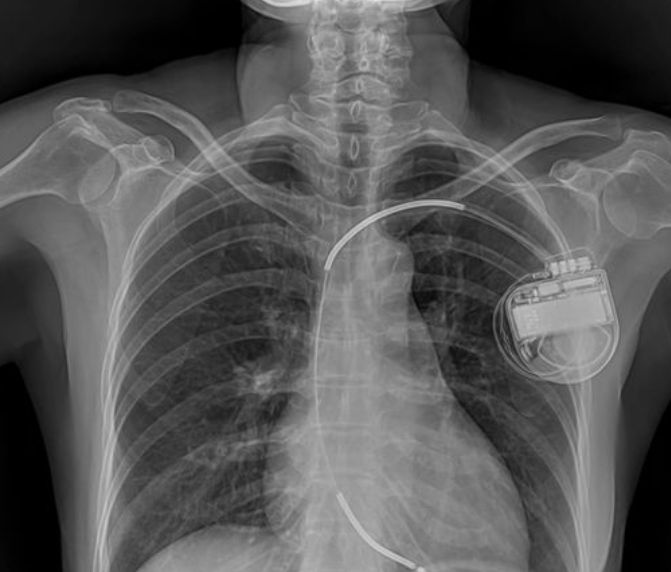

Первый имплантируемый кардиостимулятор создали в 1958 году шведские кардиохирург Оке Сеннинг и инженер Руне Эльмквист. Он был установлен пациенту с полной блокадой сердца в Каролинской больнице в Стокгольме.

Кардиостимуляторы регулируют работу сердечной мышцы с помощью электрических импульсов.

Современные кардиостимуляторы работают до 10 лет без замены батареи и управляются дистанционно.